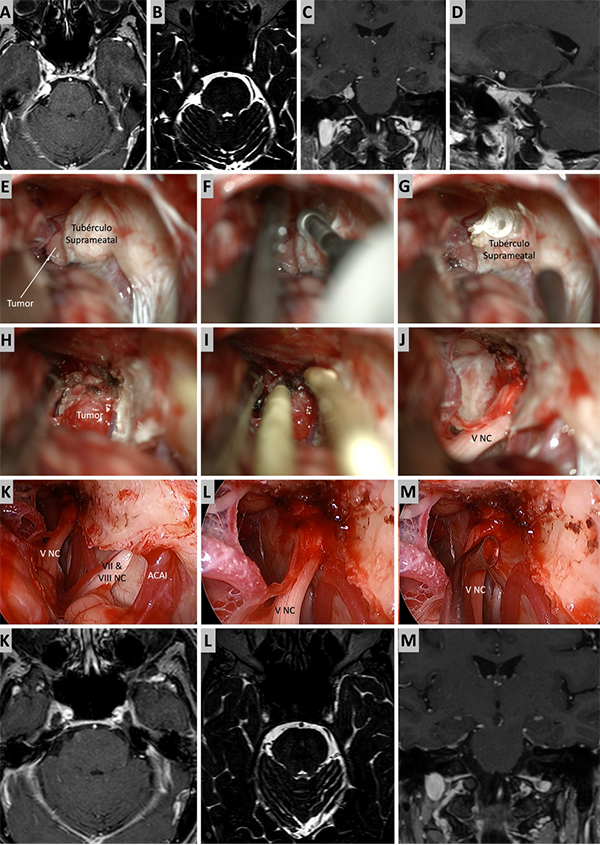

Figura 4. Caso ilustrativo #2. MRPC con implantación petroclival, extensión a la fosa media y compromiso de la incisura tentorial. Paciente con audición conservada. A. Corte axial sobre la región clival media. B. Corte axial sobre la región clival superior. Corte Coronal. D. Corte sagital donde se observa el efecto compresivo sobre el tallo cerebral. E-J. Se realizo un abordaje retrosigmoideo. K-N. Se muestra las imágenes en distintos cortes con resección quirúrgica completa.

Figura 5. Caso ilustrativo #3. A-D. Resonancia que muestra MRPC con implantación clival. E-J. Se realiza un abordaje retrosigmoideo, consiguiendo la liberación del complejo VII-VIII del tumor y su resección completa. K-M. Resultado imagenológico postquirúrgico.

Figura 6. Caso ilustrativo #4. Meningioma de la MRPC con implantación petrosa anterior. El paciente presentaba neuralgia del trigémino atípica derecha. A-D. Imágenes por RMN pre operatorias. E-J. Se realiza un abordaje retrosigmoideo consiguiendo la resección total del tumor. K-M. Con ayuda de endoscopio y lente con angulación de 30º se inspecciona el área sin encontrar remanente tumoral. Se observa liberación del nervio trigémino. K-M. RMN postoperatoria que muestra resección total.